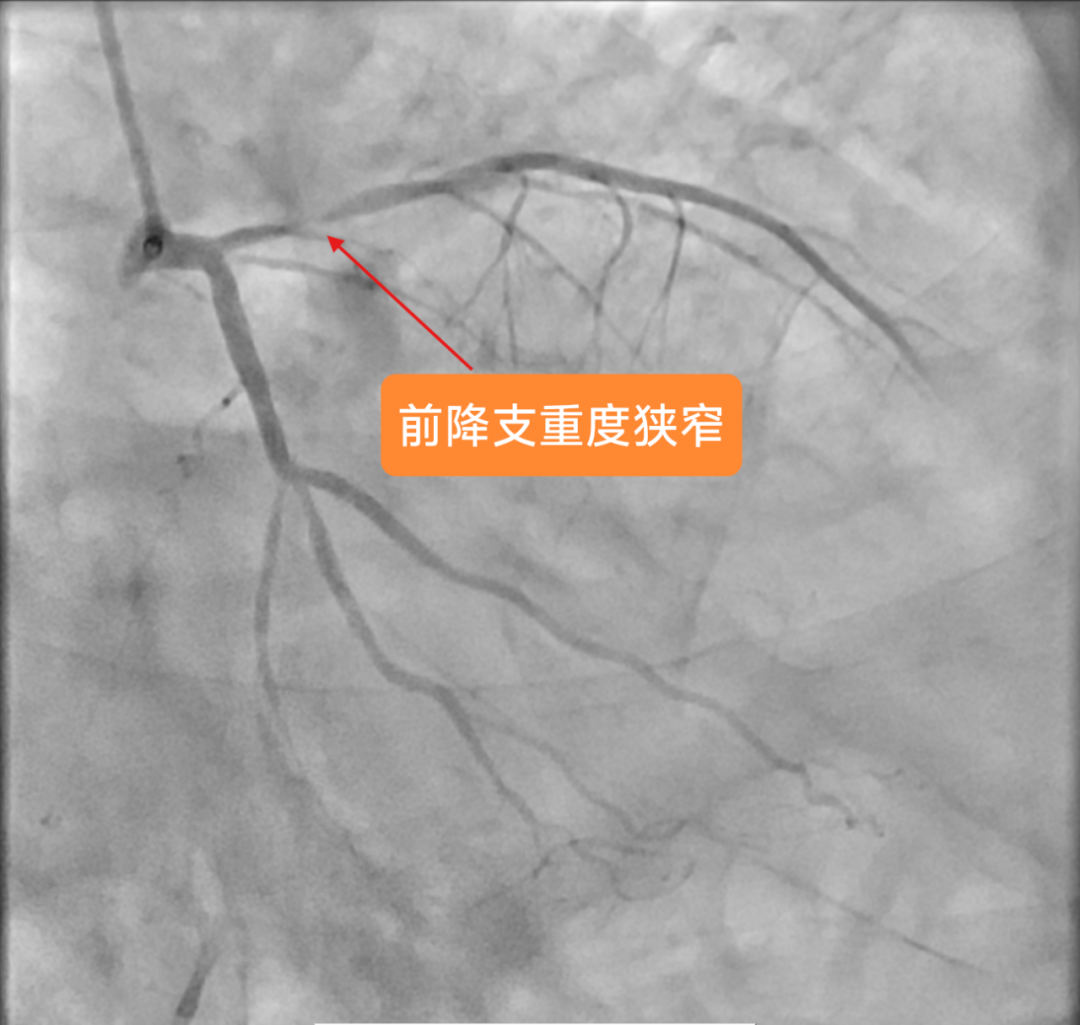

在征得家属同意后,医疗团队优先为罗先生实施心血管手术。然而,就在准备植入支架的紧要关头,患者突发室颤导致心跳骤停。经验丰富的手术团队临危不乱,立即启动应急预案,果断实施胸外按压,并给予两次精准电击除颤。在惊心动魄的几分钟后,罗先生的心脏终于恢复搏动。稳住患者生命体征后,玉溪市中山医院心内科业务主任李驹凭借精湛的医术,精准、迅速地将支架植入堵塞血管。随着支架成功撑开,停滞的血流瞬间恢复通畅,罗先生的心脏危机暂时得以化解。

支架植入后,患者前降支血管血流恢复通畅